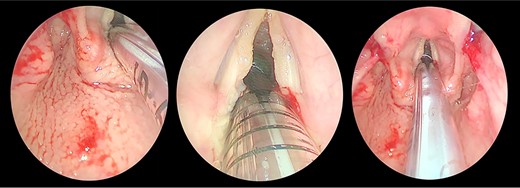

Direct laryngobronchoscopy showing a polypoidal lesion on the middle third of the left vocal fold with a granular appearance of the interarytenoid region and cobblestoning of the posterior pharyngeal wall.

The patient underwent direct microlaryngoscopy (MLS) with multiple biopsies under general anesthesia. MLS revealed the same previous findings with a clear subglottic area (Figs 1 and 2). Multiple biopsies were obtained from the mentioned regions using punch forceps. There were no intraoperative or postoperative complications. The patient was discharged in stable condition the following day.